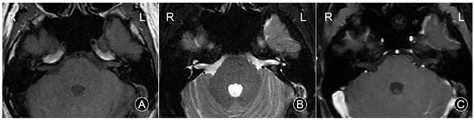

病理:(左侧内听道)送检病变组织中富于静脉血管,管腔扩张,部分管壁平滑肌较厚(图2),考虑血管瘤,静脉型。

病理:(左侧内听道)送检组织切面灰红色,镜下见增厚扩大的静脉血管壁,内衬覆扁平的血管内皮,部分血管腔内见散在红细胞,考虑静脉型血管瘤,周围伴骨组织。

文献报道[3]IAC血管瘤高发于中年人,中位年纪38岁。本组2个病例的发病年龄为31及34岁,与文献结果相近。镜下,VH病变内可见明显扩大畸形的静脉血管壁,血管壁由疏松聚集的梭形细胞和增厚的血管平滑肌细胞组成,周围见胶原-黏液样细胞外基质,符合VH的典型组织病理学表现。